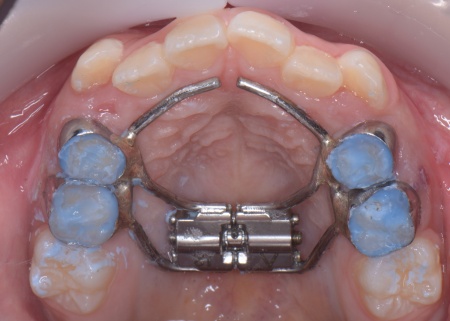

メリット デメリット また、治療にあたりお口全体のバランスを確認したところ口元の突出はなく、顎のサイズはやや小さめですが、成長期であることから歯列の拡大が可能な状態だと判断しています。 以上の内容について丁寧に説明し、治療に同意いただきました。 まず、上顎に顎の骨を広げるための固定式の矯正器具「急速拡大装置」を、下顎には歯並びの幅を広げるための「リンガルアーチ」を装着します。 次に歯の位置を整えるため、ワイヤー矯正を開始します。 最後に、歯並びが整って見た目や噛み合わせにも問題がないことを確認し、装置を取り外して第1期矯正治療を終了しました。 現在も経過観察を継続していますが、歯が元の位置に戻る後戻りも見られず、残っている乳歯から永久歯への生え変わりも順調に進んでいます。 |